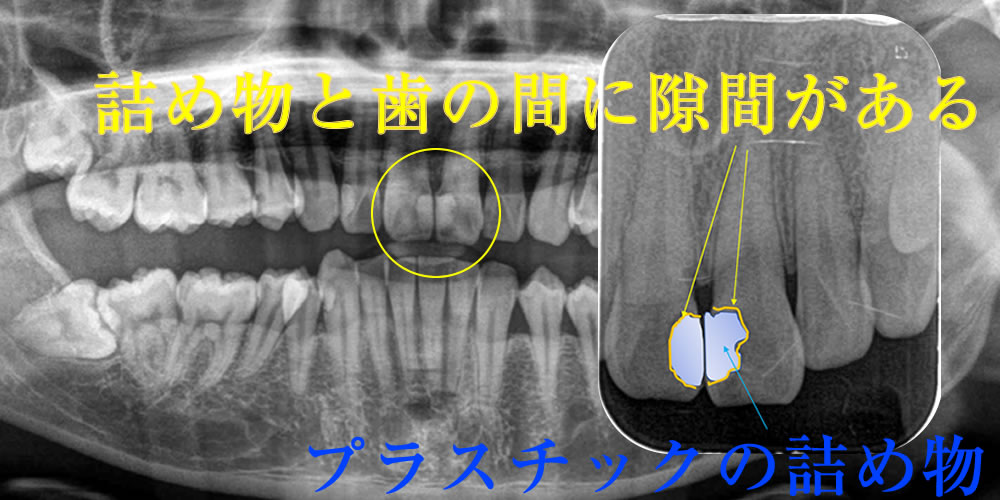

正面(写真左)から見ると、何も異常がないように見えますが、上顎前歯の裏側(隣り合った歯と歯の接触している部分)が虫歯になっていました。

レントゲンで虫歯部分を確認

レントゲンで確認すると、以前の治療で修復した部分に隙間が生じていました。詰め物と虫歯感染歯質を丁寧に取り除いていきます。

虫歯除去後にCRを充填して治療完了

象牙質まで達していた虫歯(C2/中度虫歯)を、丁寧に取り除いた後にCRを充填して治療完了です。CR(コンポジットレジン)による虫歯治療は、一度の治療で完治していますが、なるべく長持ちさせるために患者様ご自身で、術後の管理(今回の場合は歯ブラシ+フロスの使用など)と定期的な歯科医院でのチェックが必須になります。